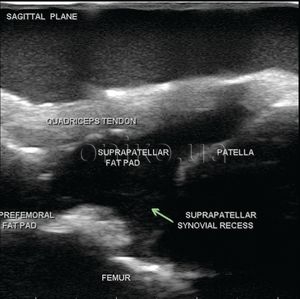

Tento model obsahuje distální část stehna, proximální část tibiální a fibulární kosti, hamstring, šlachu čtyřkolového svalu, stehenní tukové tkáně, čtyřkolové tukové tkáně, bursy a kloubní kapsle

Celá anatomie poskytuje možnost podrobného zpracování laterálního středního podkolenního přístupu k provádění injekcí kolenního kloubu pomocí ultrazvuku